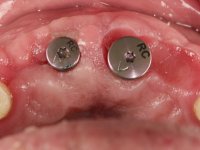

Segunda Fase

6 meses após a colocação da ponte, o paciente sofre um novo traumatismo comprometendo a viabilidade dos dentes 1.2 e 1.1. Foi realizada uma prótese removível acrílica para reabilitar provisoriamente o paciente enquanto foram extraídos os dentes 1.2 e 1.1 e foi colocado o implante no local do dente 1.1. Passados 3 meses foi realizada uma impressão ao implante colocado no 1.1 e simultaneamente foi feito um arrasto da ponte dos dentes 2.1 e 2.2. Para esse efeito no implante 2.1 foi utilizado um parafuso de uma peça de transferência. Dessa forma conseguiu-se impressionar corretamente a arquitetura gengival do sector antero-superior. O objetivo era simultaneamente impressionar corretamente esta zona e aproveitar a estrutura metálica desta ponte para confecionar a nova ponte de 4 elementos. Foi colocado um parafuso de cicatrização no implante 2.1 e foram acrescentados os dentes 2.1 e 2.2 na prótese removível. Com perícia laboratorial foi criada uma nova infraestrutura metálica de 4 elementos assente nos implantes 1.1 e 2.1 e com os elementos pônticos suspensos 1.2 e 2.2. No implante 2.1 manteve-se a conexão interna ao implante no implante 1.1 optou-se por uma peça intermédia facilitando a inserção da infraestrutura. A nova infraestrutura foi verificada em boca. Como pode ter havido alguma alteração da arquitetura gengival com a remoção da ponte e colocação do parafuso de cicatrização no 2.1, foi feita uma chave de silicone para permitir uma impressão de arrasto da infraestrutura metálica. Uma nova gengiva artificial foi realizada no modelo de trabalho de acordo com esta impressão de arrasto. Foi colocada cerâmica de tonalidade coronária e gengival. A peça protética foi aparafusada lentamente em boca para permitir uma adaptação dos tecidos moles. Após o correto assentamento e verificação imagiológica a ponte foi definitivamente apertada em boca e os orifícios de acesso obturados. Independentemente dos infortúnios que o paciente teve, pude ter a satisfação de o ver contente com esta reabilitação.